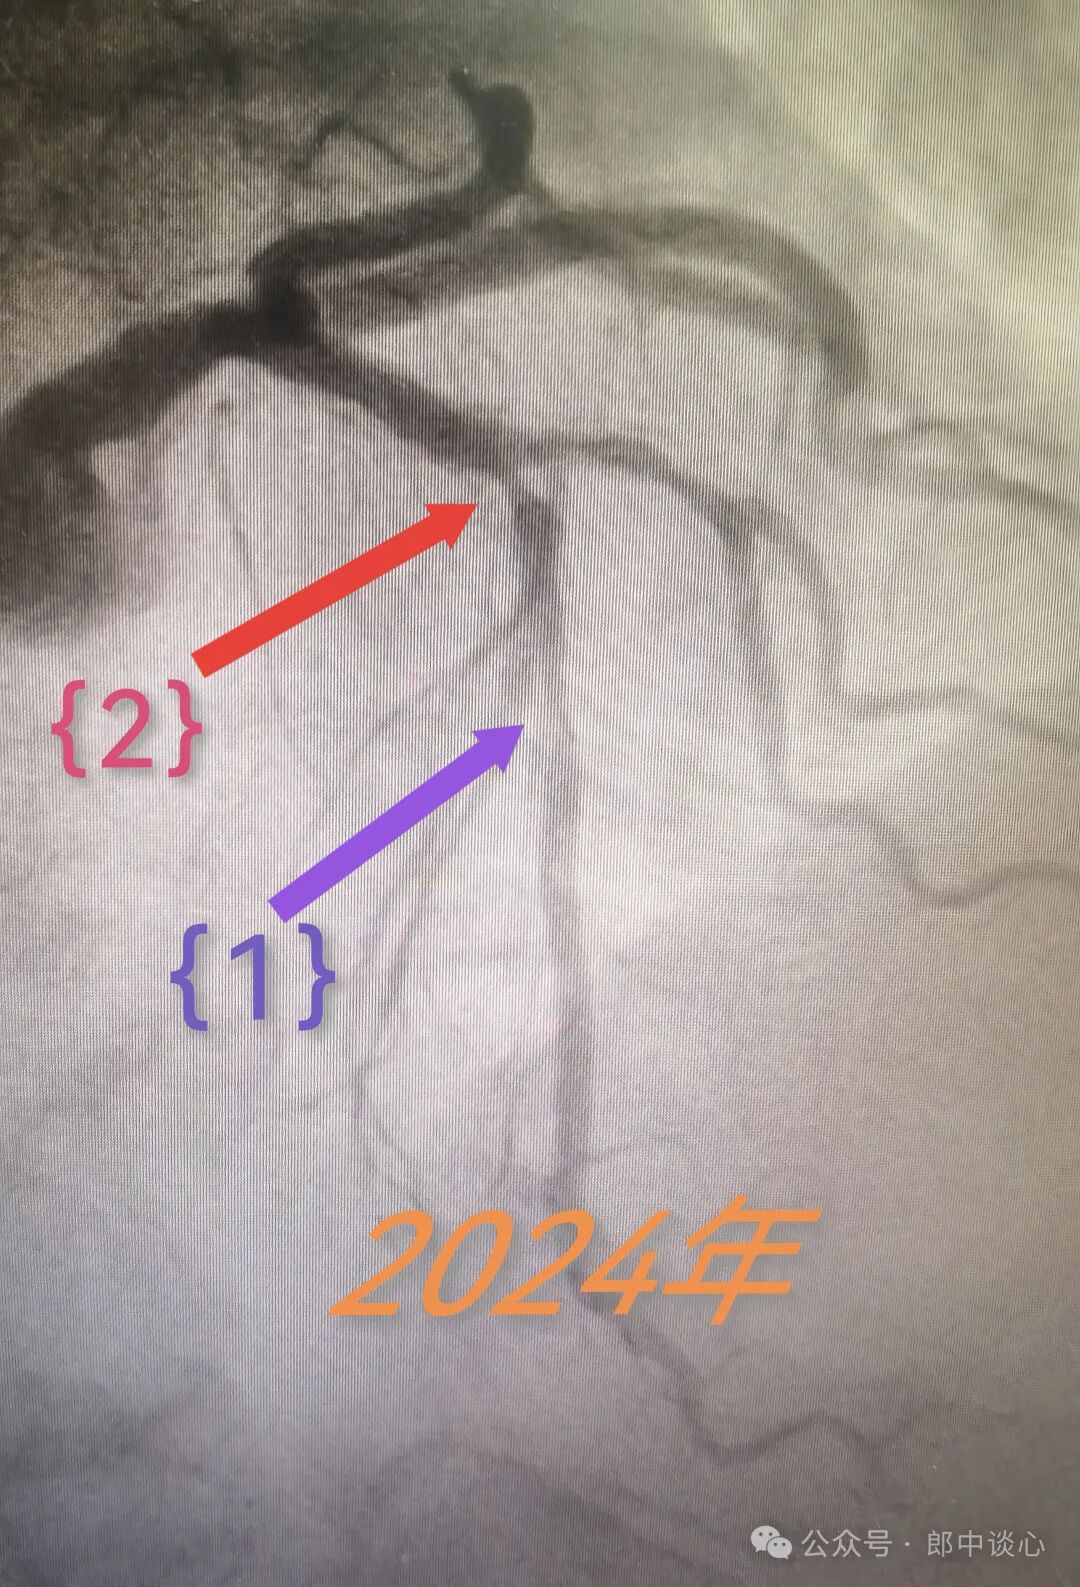

再做造影,六年前PTCA的对角支保持得还不错,{1}部位似乎还是六年前的那个临界病变,但前降支{2}部位出现了一个“新”的病变!

难道{2}就是他本次的犯罪病变?或者说他本次缺血心绞痛发作是与{1}病变的叠加效应?

假定是这样,是不是这次只需要处理病变{2}就可以了?继续不动病变{1}?